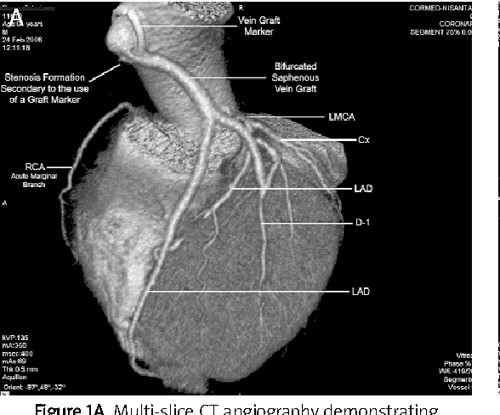

Cabg thesis topics image This image demonstrates cabg thesis topics.